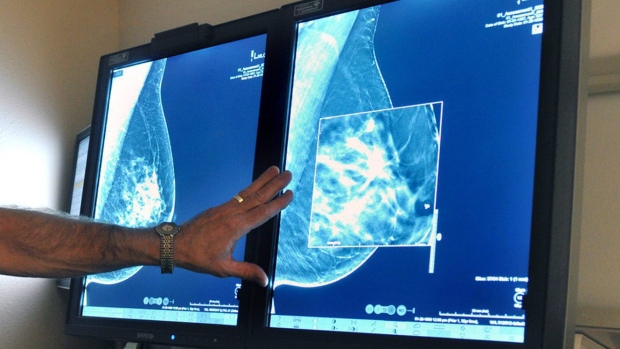

加拿大 BC省刚刚公布了一项新研究,研究显示,在定期进行乳腺癌的检查上,BC 省的移民妇女不像本土出生的妇女那样 “积极”。

BC 省癌症协会和不列颠哥伦比亚大学 UBC 联合进行了这一调查,并发表在癌症医学杂志 (Cancer Medicine)上,这一为期两年的研究发现,妇女定期接受乳腺癌检查的比例,因其出生国而有很大不同。

报告的主作者 Ryan Woods 说, 我们的研究表明,移民妇女去定期接受乳腺癌检查的比例低于非移民妇女,但一些特定族群更加明显。

在非移民妇女群体中, 51.2% 的妇女定期进行乳腺X光检查,但来自东欧和亚洲国家的的移民妇女,这一比例较低:

- 东欧/中亚移民妇女 – ?33.9%

- 韩国裔移民妇女 – 39%

- 印度裔移民妇女??– ?44.5%

- 华人 移民女性 – ?45.7%

- 菲律宾移民女性 ?– ?45.9%